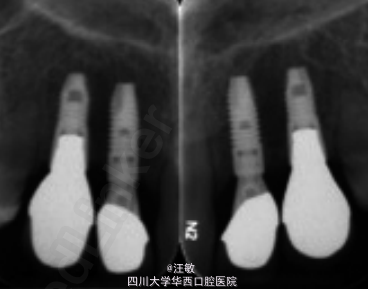

诊断模型进行分析,上中切牙间隙约2mm,左侧乳侧切牙和乳尖牙修复空间为17mm,右侧为15mm。基于患者乳牙有牙根吸收,建议拔除所有滞留乳牙,其后进行种植修复。上切牙冠修复。面弓转移记录颌位关系。

此病例中患者拔除滞留乳牙后原则上可进行活动义齿修复,但可能增加牙菌斑堆积不利于牙周清洁。固定桥修复跨度较大,且前磨牙有扭转,算是一种“破坏性”修复方式。在此情况下,种植修复不失为一个较好的选择,而且患者牙槽骨条件较好,适合进行种植手术。临床中一定要根据患者情况选择最佳的修复方案。doi: 10.1002/ccr3.213